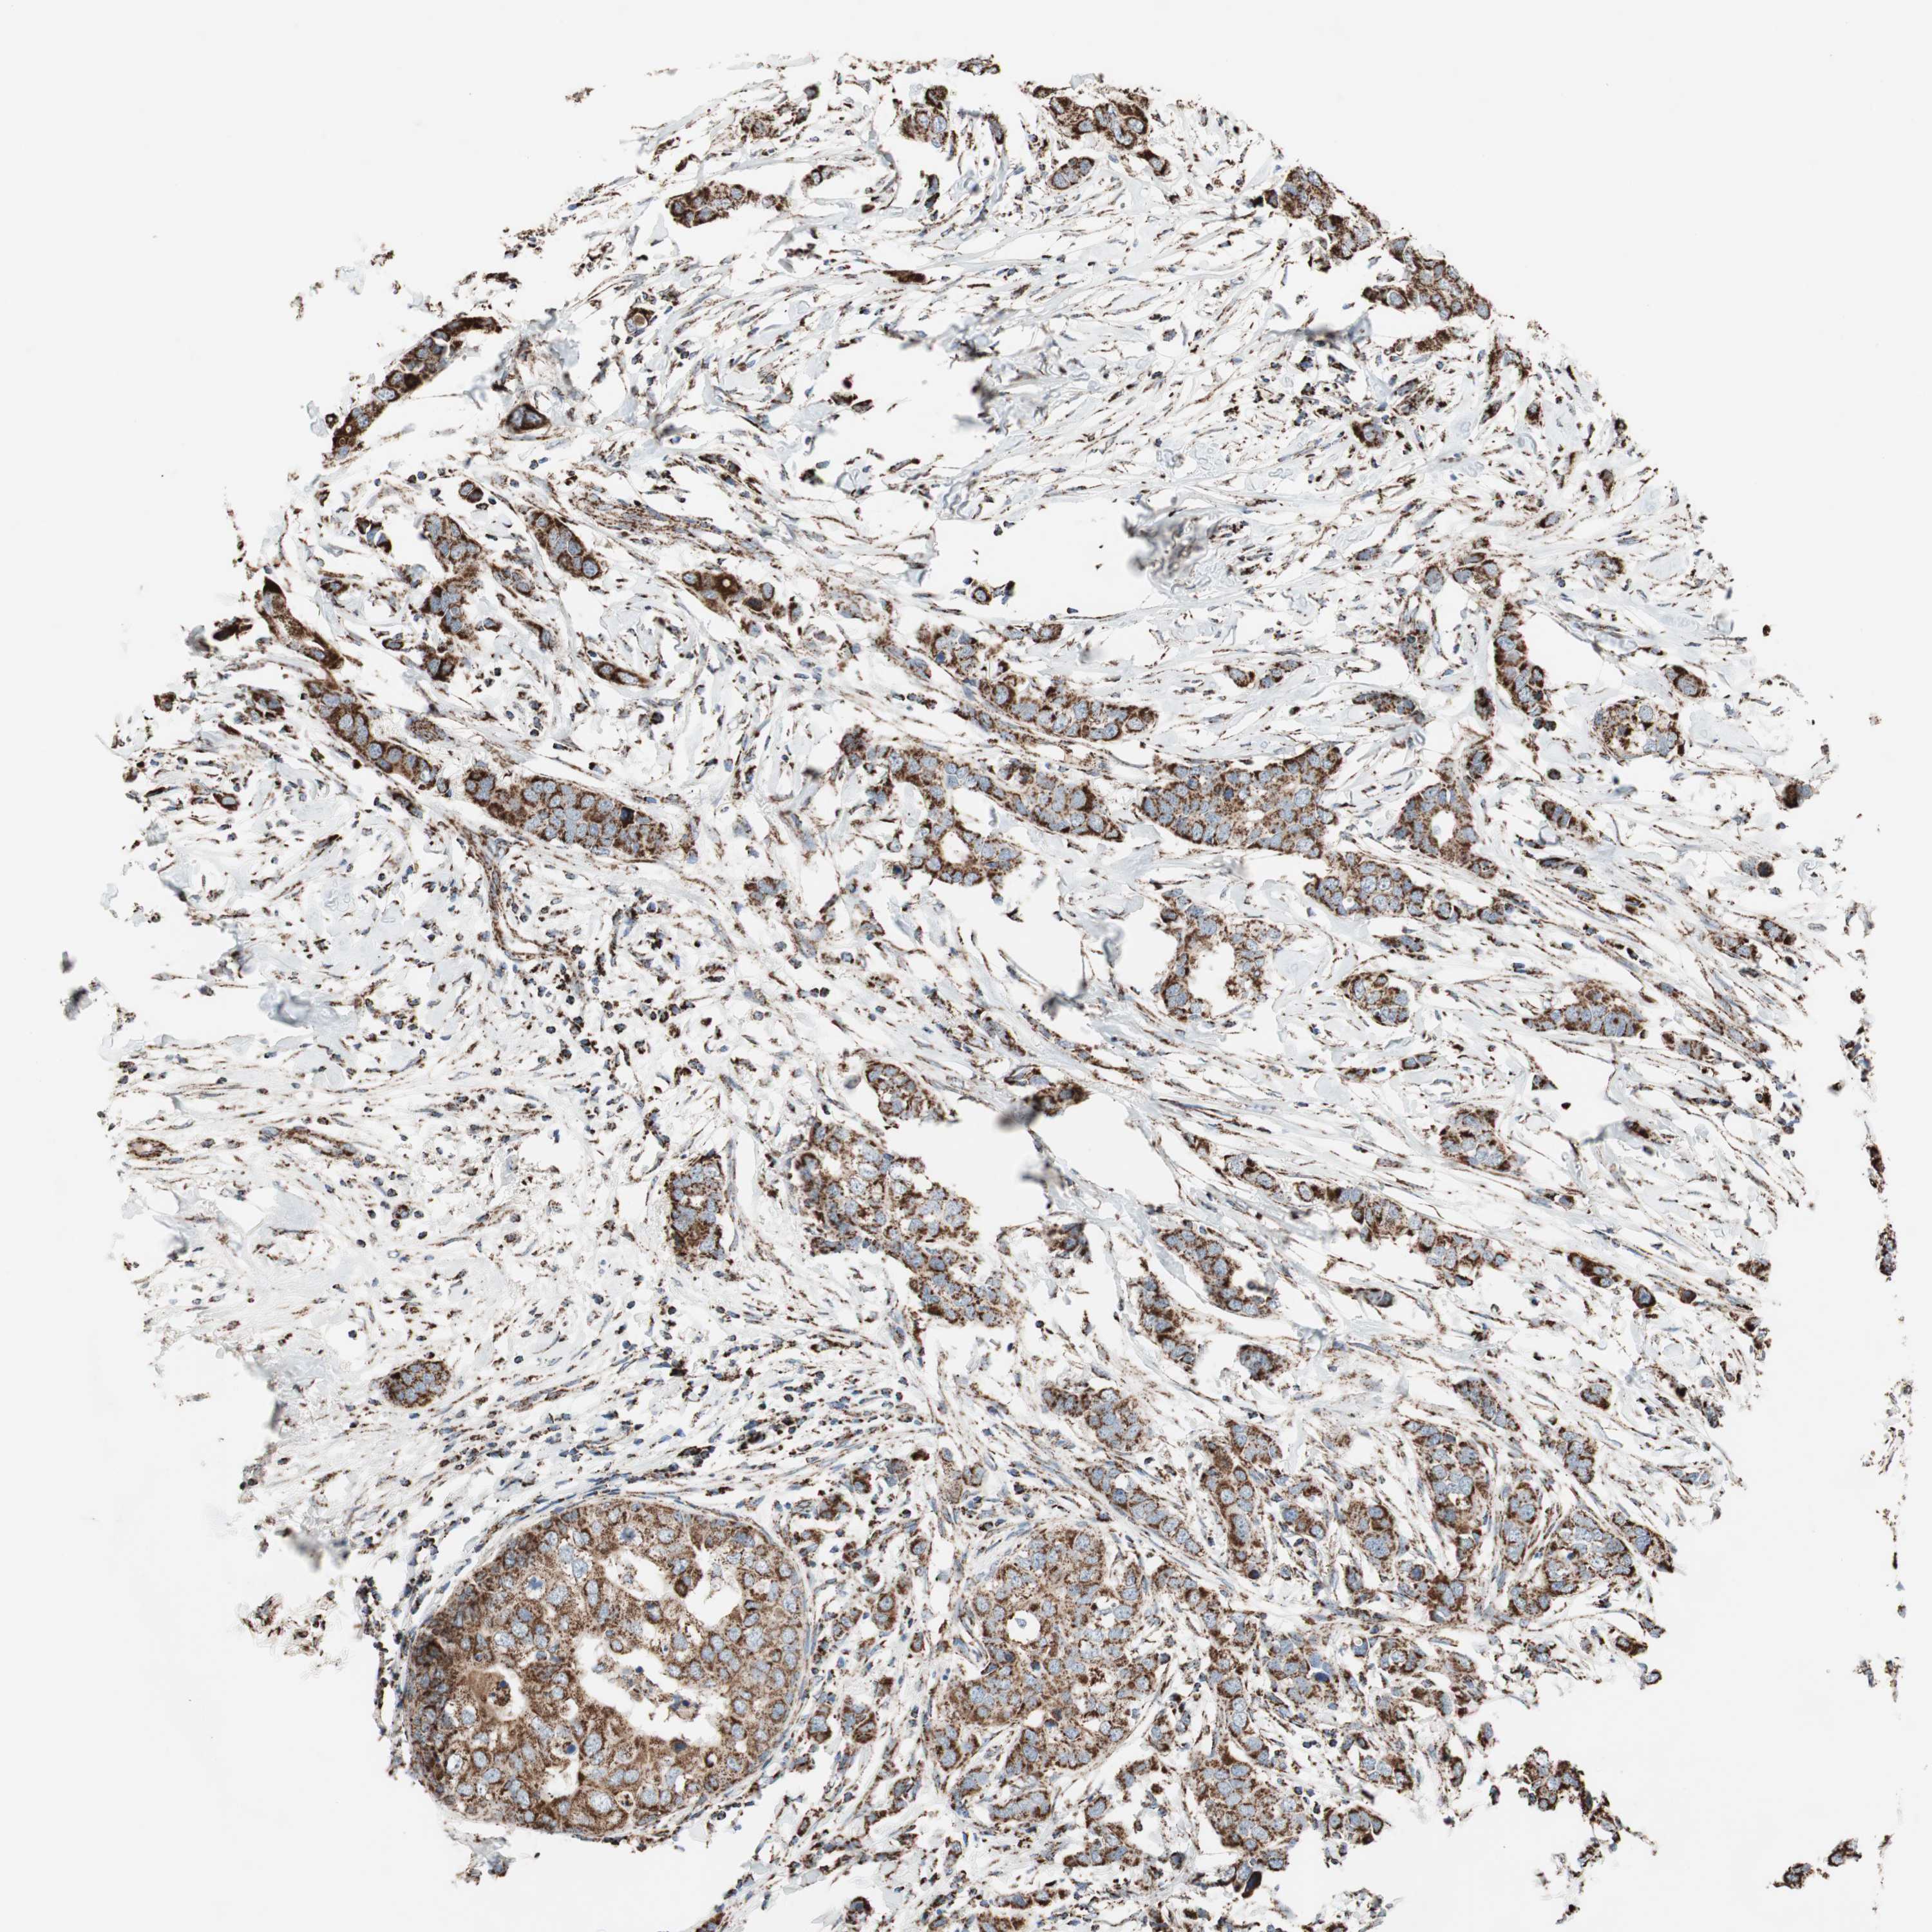

CANCER BREAST CANCER Show tissue menu

BRCA TCGA BRCA VALIDATION PROTEIN EXPRESSION